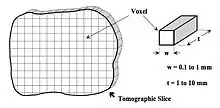

Image Reconstruction Basics

- A cross-sectional layer called a tomographic slice of the body is obtained by dividing it into many tiny volume elements called voxels - see Figure 7.10. When displayed on a computer screen, each voxel is represented in two dimensions by a pixel. The task in CT is to assign a number to each voxel that is proportional to its X-ray attenuation. This can be achieved by rotating an XRT and an array of detectors around the slice of interest to measure the radiation intensities projected at different angles around that slice. In other words, multiple views around the slice are acquired. An image reconstruction algorithm is then applied to this projection data to estimate the attenuation in each voxel. The amount of attenuation for a voxel is determined by its composition and size, along with the X-ray energy, and is characterised by a parameter (which can be expressed in Hounsfield Units, HU) derived from the linear attenuation coefficient, μ.